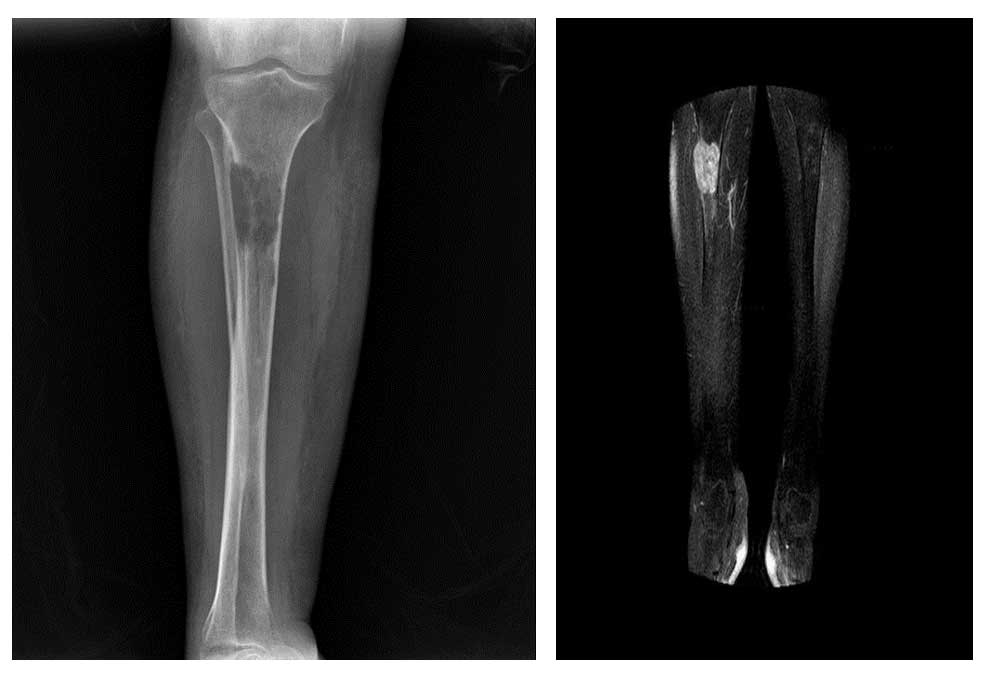

Görsel Açıklamaları

Ameliyat Öncesi: Röntgende sağ tibia üst uç dış kısımda yeniklik/harabiyet ve kırık riski, MR’da aynı lokalizasyonda tümör dokusu görülmekte.